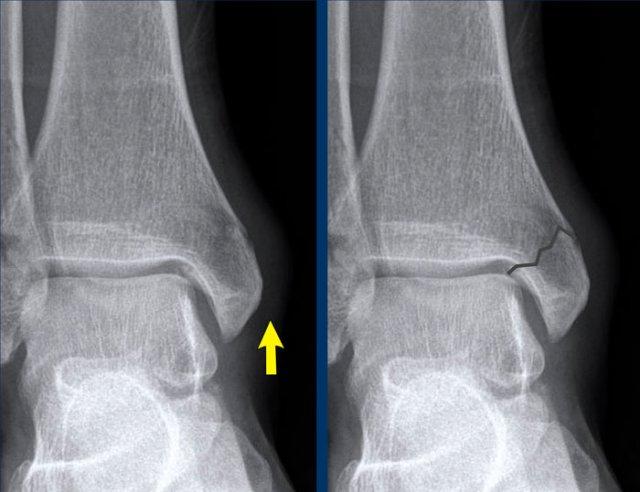

case 2 – distortion

Trong trường hợp này, phát hiện rõ ràng nhất là gãy mắt cá sau.

Điều này cần thúc đẩy bạn tìm kiếm các phát hiện khác, vì gãy mắt cá sau đơn độc là cực kỳ hiếm gặp và có thể không tồn tại.

You need to look at the algoritm for ankle fractures..

Algoritm for ankle fractures

Trong thuật toán, gãy mắt cá sau là một trong hai trường hợp:

- Giai đoạn 3 của gãy xương Weber B

(còn gọi là Ngửa-Xoay ngoài theo phân loại Lauge-Hansen) hoặc - Giai đoạn 4 của gãy xương Weber C

(còn gọi là Sấp – Xoay ngoài theo phân loại Lauge-Hansen)

Điều này có nghĩa là chúng ta phải tìm kiếm các dấu hiệu khác.

Vì không có dấu hiệu của gãy xương Weber B, đây phải là gãy xương Weber C.

Có những dấu hiệu nào khác ủng hộ chẩn đoán gãy xương Weber C không?

Có.

Bây giờ chúng ta nhận thấy sưng nề mô mềm ở phía trong và một mảnh avulsion nhỏ, đây là giai đoạn 1 của tổn thương này.

Chúng tôi hiện có thể dự đoán gãy xương mác cao, điều này đã được xác nhận bằng chụp X-quang toàn bộ cẳng chân.